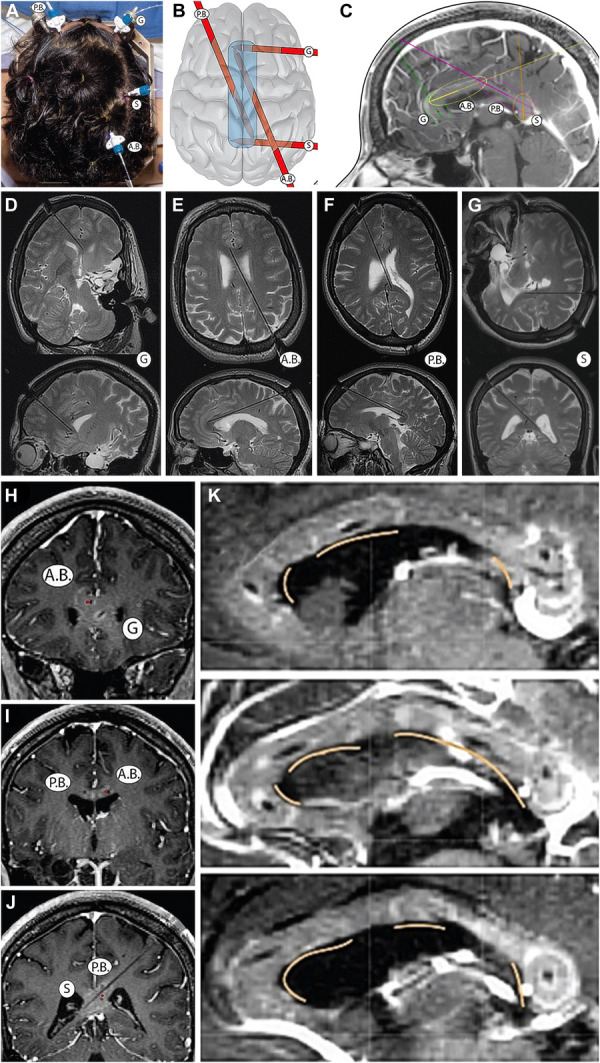

В 1960-х–70-х годах нейробиолог Майкл Газзанига работал с необычными пациентами. Им была сделана каллозотомия — хирургическое рассечение мозолистого тела (corpus callosum), главного коммуникационного тракта между полушариями, содержащего около 200 миллионов аксонов. Операция применялась для лечения тяжёлой эпилепсии.

После рассечения полушария переставали «разговаривать» друг с другом. Это открыло уникальную возможность: изучать их работу независимо.

Газзанига и его коллеги разработали элегантные эксперименты. Пациент смотрит в центр экрана. В левое поле зрения — которое обрабатывается правым полушарием — на долю секунды выводится слово «лопата». Левое полушарие этого не видит. Но рука пациента тянется за лопатой — потому что моторные команды для левой руки исходят именно из правого полушария.

Экспериментатор задаёт вопрос: «Зачем вы взяли лопату?»

Левое полушарие — то, которое не видело слова — немедленно выдаёт уверенный ответ: «Хотел почистить снег во дворе».

Объяснение детализировано, убедительно — и полностью ложно. Левое полушарие просто не знало причины. Но вместо того чтобы сказать «не знаю», оно придумало историю. И само в неё поверило.

Газзанига описал этот феномен в книге «Кто за главного? Свобода воли с точки зрения нейробиологии» и назвал механизм модулем интерпретатора.